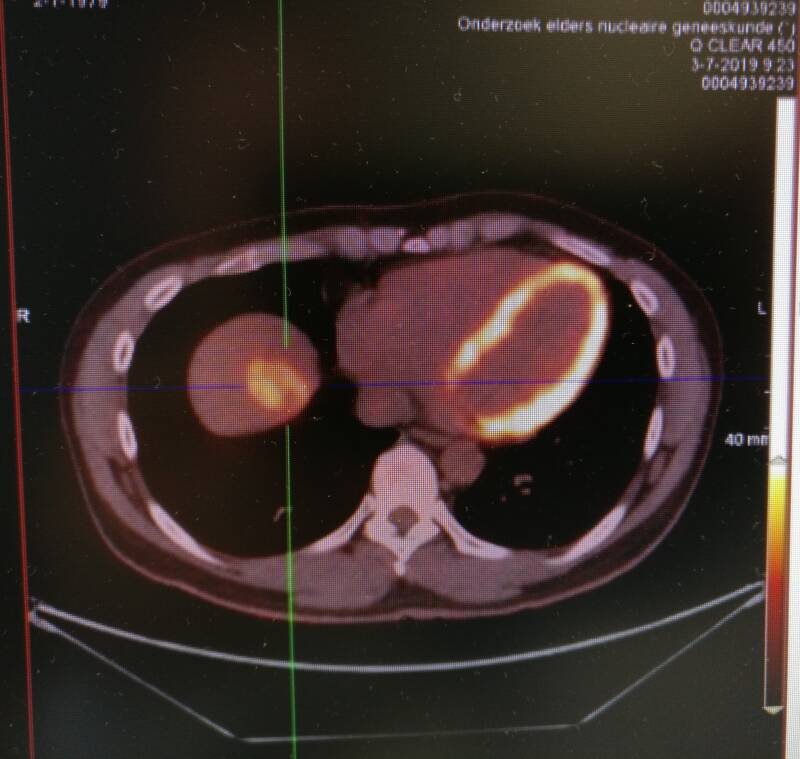

Alle foto’s zijn met mijn telefoon gemaakt van een beeldscherm, vandaar de matige kwaliteit. Allereerst een overzichtsfoto. Dit is een PET-scan. Bij een PET-scan wordt radioactieve glucose (suiker) in mijn lichaam ingespoten. Hierdoor lichtten de delen op die actief zijn en suiker vragen. Bovenin mijn hoofd zijn dat mijn hersenen. Links in het middenrif (rechts op het plaatje, de grote bol) is mijn hart. Daarnaast zit de tumor, links op het plaatje, rechts in mijn borstkas. Duidelijk te herkennen door het kruis wat erdoorheen is gezet. Het donkergrijze gebied onder de tumor is mijn lever en daar weer onder kun je ook goed mijn twee nieren herkennen. Tenslotte zie je dat het plasmiddel goed werkt, want mijn blaas (de onderste donkere bol) zit al vol met radioactief afvalmateriaal. Op een PET-scan zie je de actieve delen in het lichaam heel duidelijk, maar de andere weefsels en organen zijn nauwelijks te zien.

Daarom wordt met de CT-scan via de computer gecombineerd met de PET-scan. Het resultaat is een PET/CT-scan. Hierbij zie je duidelijk de tumor in mijn lever oplichten. Ook zie je dat mijn hart actief is en oplicht. De artsen kunnen letterlijk langs alle kanten door deze plaatjes scrollen en zo een duidelijk beeld krijgen van de vorm en de locatie van de tumor.